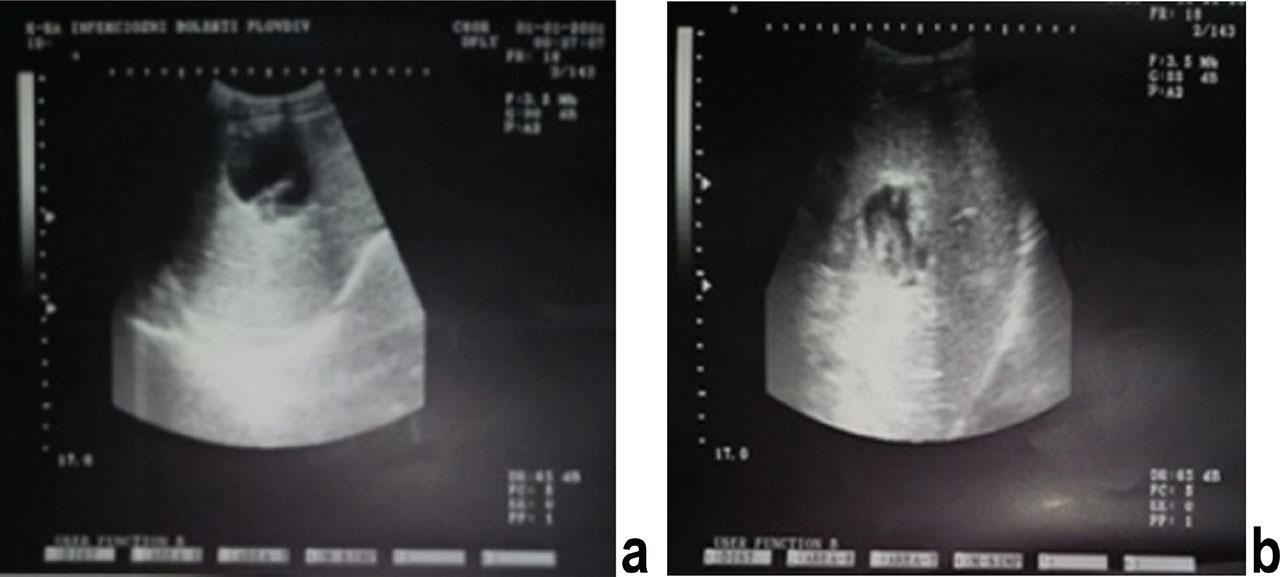

The morphological changes of the treated liver hydatid cysts were observed by imaging during the follow-up period. Six liver hydatid cysts decreased in size and their contents partially degenerated as a result of the treatment (Fig. 1). Twenty hepatic cysts became inactive (CE4) with completely degenerate contents for four to nine months (95 % CI: 6.5±0.9) (Fig. 2).

Liver hydatid cyst a) before treatment b) after 6 months combination therapy

Liver hydatid cysts a) before treatment b) after 6 months combination therapy.